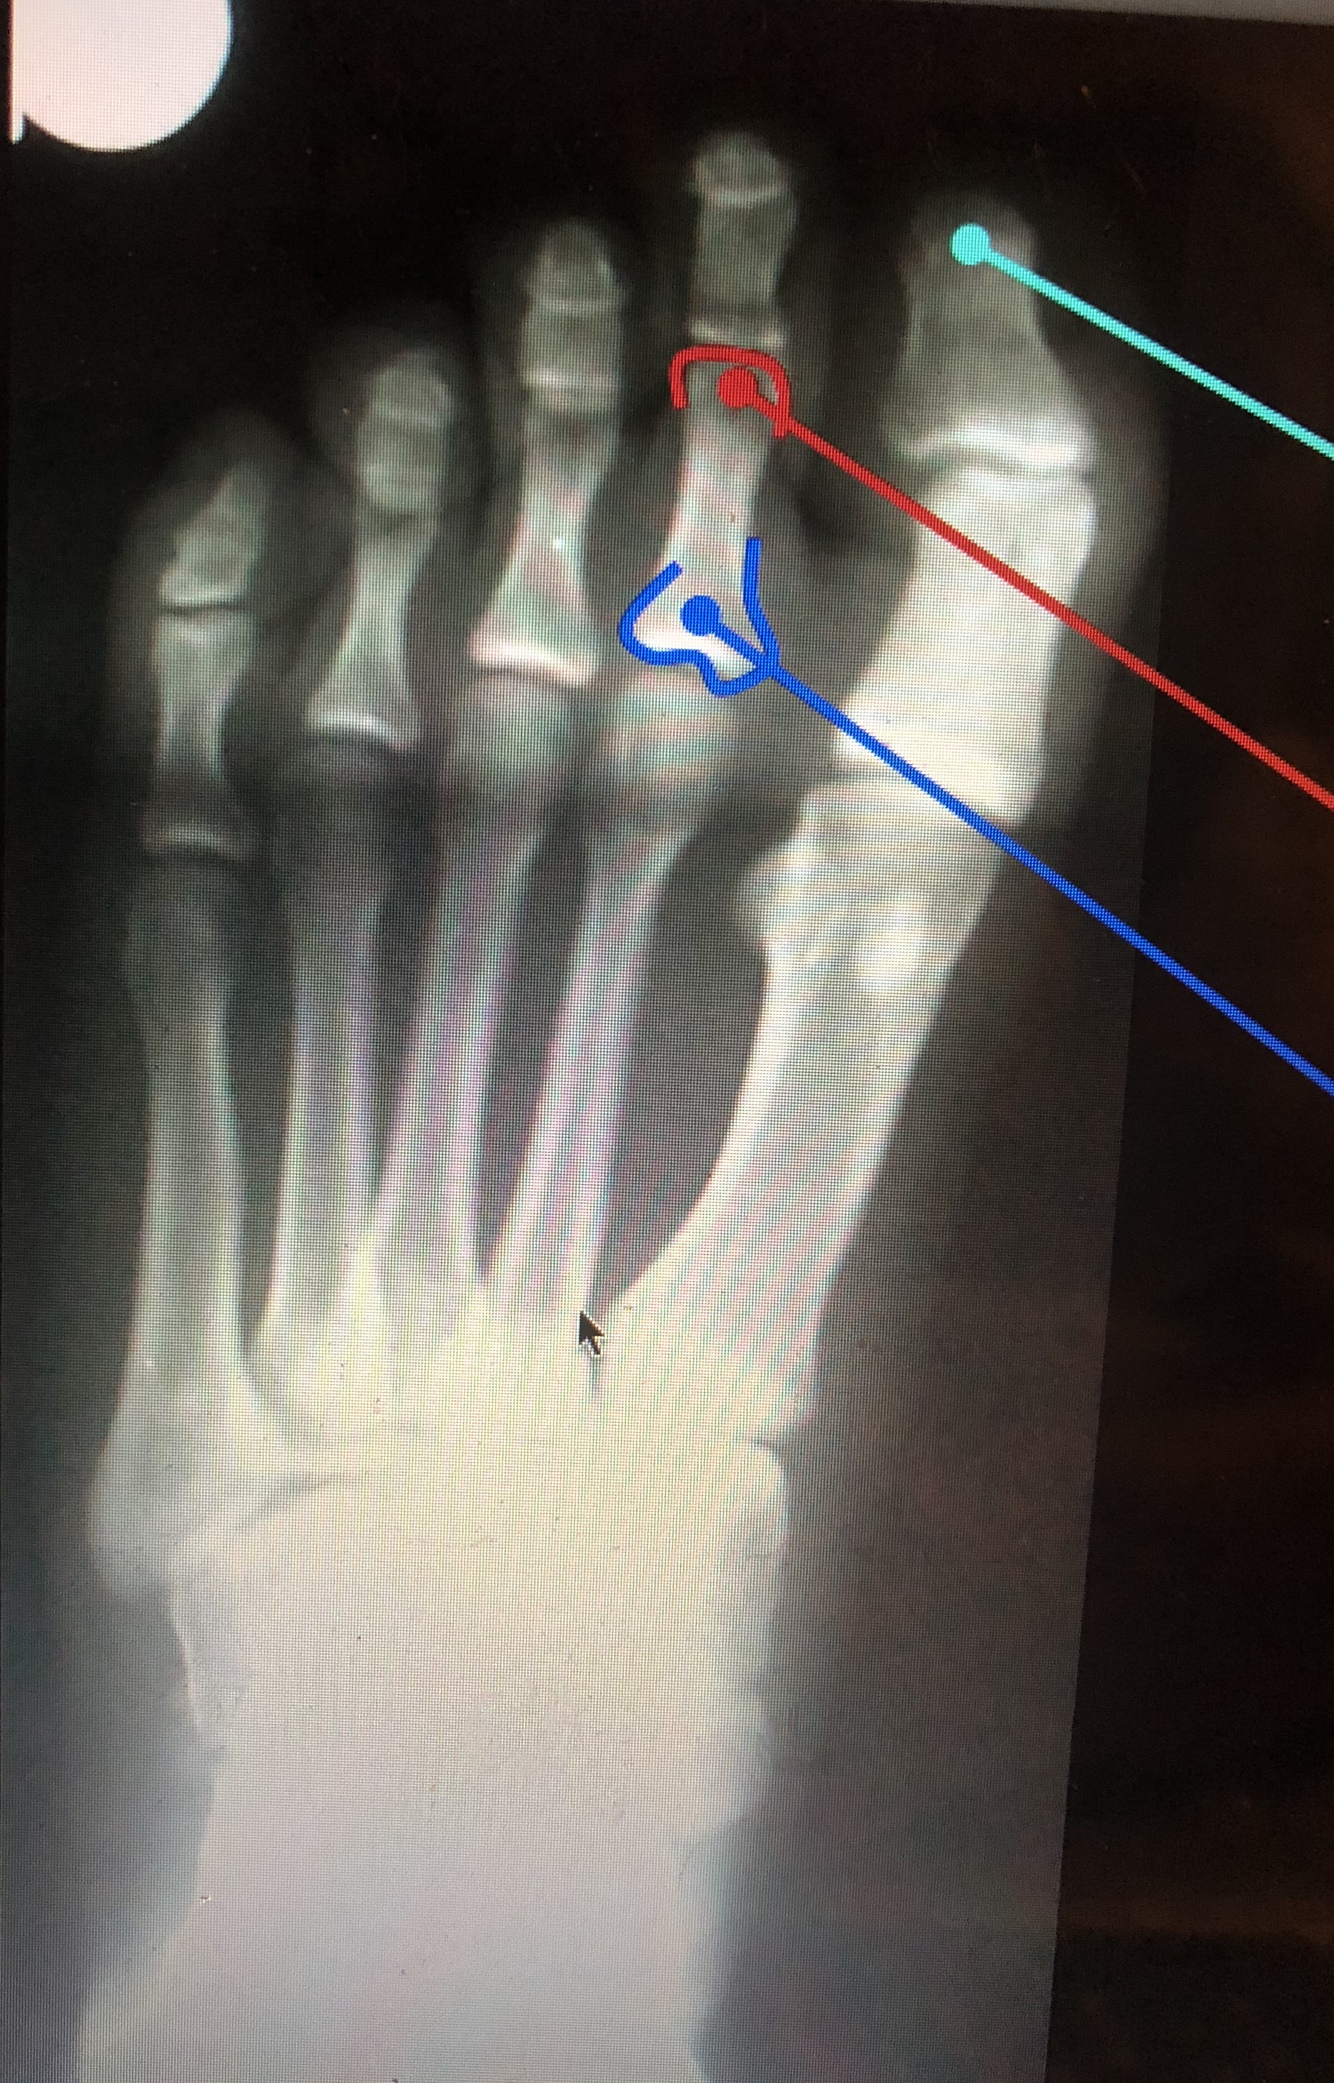

What are the top two red lines?

Sesamoid Bones

•Found in the tendon of the flexor hallucis brevis

What bone is dark blue?

Calcaneus

What bone is the bottom red line?

Talus

What is the light blue lines?

Lateral Malleolus

What is the yellow line?

Medial Malleolus